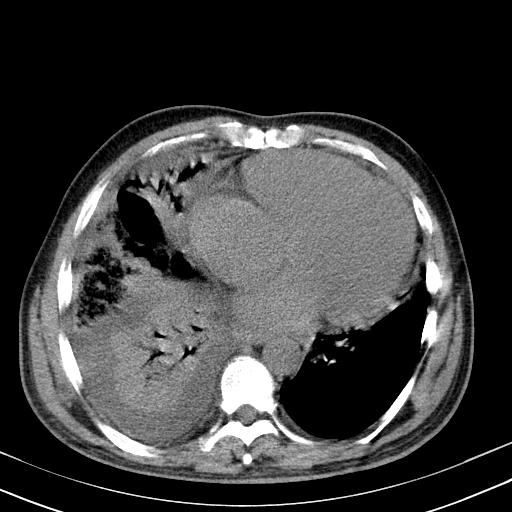

以下是引用zxl51642在2010-3-21 17:06:00的发言:[br]右下中心型肺癌并阻塞性肺炎/不张,纵膈淋巴结肿大,右侧大量胸腔积液,左侧少量胸腔积液,少量腹水。建议纤维支气管镜进一步检查。